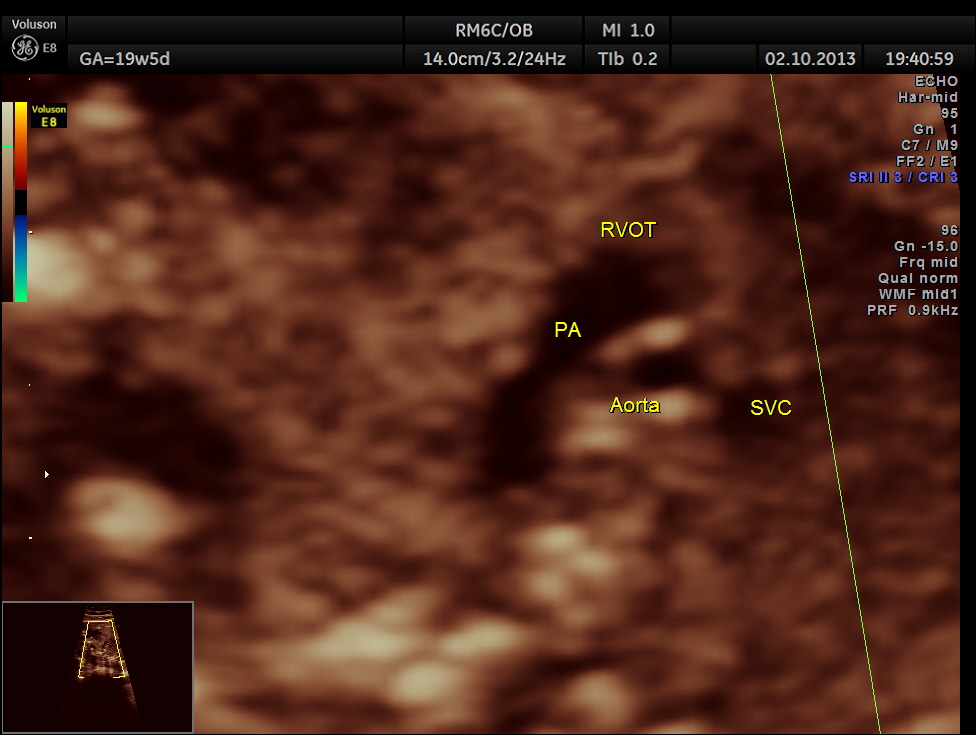

The following pictures show that the left ventricle appears smaller than the right ventricle. The situs is normal.

Colour flow also rules out the possibility of hypoplastic left heart syndrome.

Co-arctation of Aorta has the following important features in the ultrasound :

The 4 chamber view is abnormal – LV is smaller than RV.

The 3 vessel trachea view depicts great vessel disproportion. Pulmonary artery is bigger than aorta .